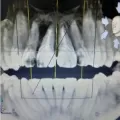

Здравствуйте. Просьба ответить, есть ли на снимке на нижней семерке слева киста. В настоящее время зуб удален. Нарушена чувствительность слева подбородка и губы. Врач утверждает, что киста проросла в нижнечелюстной канал, в этом причина. Была одновременно с удалением проведена имплантация шестерок нижних и слева за удаленной семеркой также установлен имплант (на месте восьмерки). Действительно ли была киста или причина неврита в имплантах (два из них на 0,5 мм выходят в канал). Имплантация была проведена 25.11.2013 г. и удаление зуба также.

Добрый лень. Кисты я не вижу. Онемение может быть связанно как по причине не корректной установки имплантатов так и от анестезии. Выложите снимки с имплантатами и я вам все расскажу. Всего доброго.